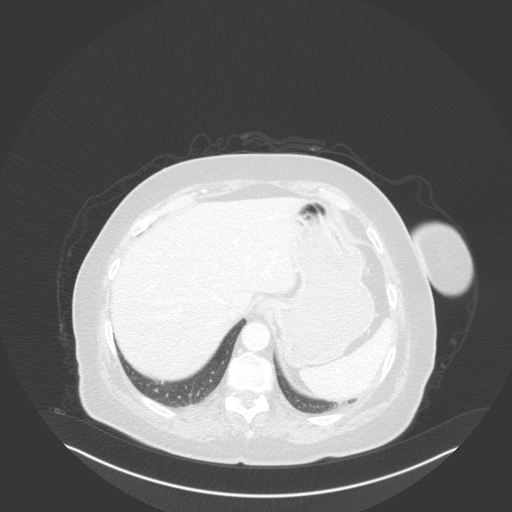

Image Grid

4Γ—3 grid: Rows show different image types (Original NATIVE, Reconstructed NATIVE, Original VENOUS, Generated VENOUS), Columns show windowing techniques (No Window, Lung Window, Mediastinum Window)

Original VENOUS CT scan

Full window (WL 1023.5, WW 4095 β†’ Low βˆ’1024, High +3071)

Lung window (WL -600, WW 1500 β†’ Low βˆ’1350, High +150)

Mediastinum window (WL 40, WW 400 β†’ Low βˆ’160, High +240)